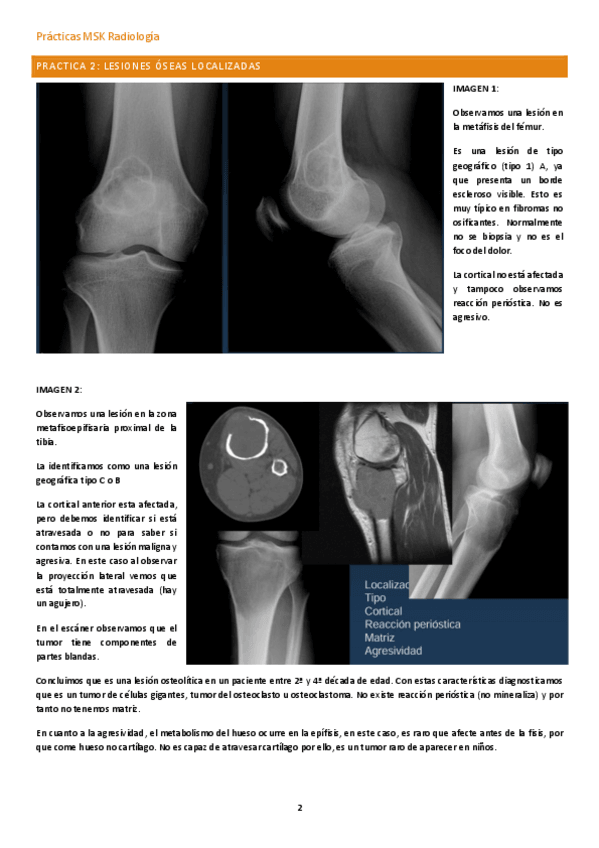

Soluciones de la 2ª práctica de musculoesquelético del curso 25-26